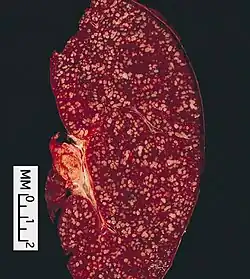

Morfología

El tumor está compuesto de folículos que contienen una mezcla de centrocitos o células clivadas del centro folicular (nomenclatura americana más vieja), "células pequeñas", y centroblastos (Kiel la nomenclatura adoptada por la OMS) o células grandes no-cliavedas del centro folicular (nomenclatura americana más vieja), "células grandes". Estos folículos están rodeados por células no malignas, mayoritariamente células T. En los folículos, predominan típicamente los centrocitos y los centroblastos son normalmente la minoría.